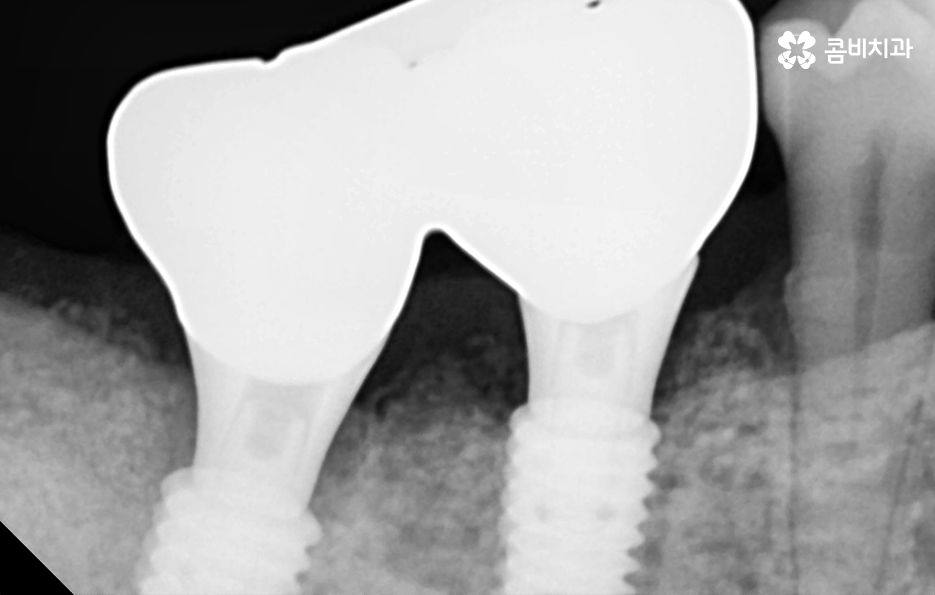

다음으로 건강보험 임플란트 혜택에 대해 알아보면 무치악 환자는 보험 적용이 해당되지 않으며 평생 치아 2개에 한하여 본인 부담금 30%만 비용을 부담하면 치료를 받을 수 있는데요. 65세 이상 임플란트에 대한 건강보험 급여 기준에 명시되어 있는 보철 재료는 PFM 크라운이며 다른 크라운 재료나 뼈이식, 상악동 거상술과 같은 부가적인 수술에 대해서는 비급여로 분류가 되어 별도의 비용을 지불할 수 있어요

임플란트의 치료 원리를 살펴보면 임플란트는 잇몸 뼈에 심고 골 유착 과정을 통해서 저작력을 얻기 때문에 치료 전과 치료 후 모두 잇몸 상태가 매우 중요한 치료라는 것을 알 수 있어요

잇몸 뼈가 부족한 경우 뼈이식을 통해 임플란트를 식립하기 좋은 잇몸 상태를 만드는 것이 치료 결과에도 중요하며 임플란트의 식립 위치부터 각도, 깊이 등은 치과의 첨단 장비뿐 아니라 치과의사의 경험과 실력이 중요한 부분이기 때문에 임플란트의 전체 과정을 고려하여 비용도 중요하지만 건강한 치료 결과를 위해 종합적으로 따져보고 치과를 선택하시길 권하고 있어요